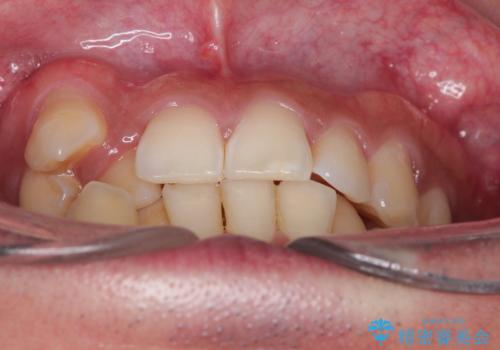

【ワイヤー矯正】八重歯と下の歯の凸凹を治したい

- 主訴:右上の八重歯と、下の歯の凸凹を治したい

上顎右側第一小臼歯と下顎右側第一小臼歯を抜歯しワイヤー矯正を行いました。

右側2級、左側1関係だったため、右側上下第一小臼歯を抜歯し、ワイヤー矯正を行いました。

期間:2年6カ月